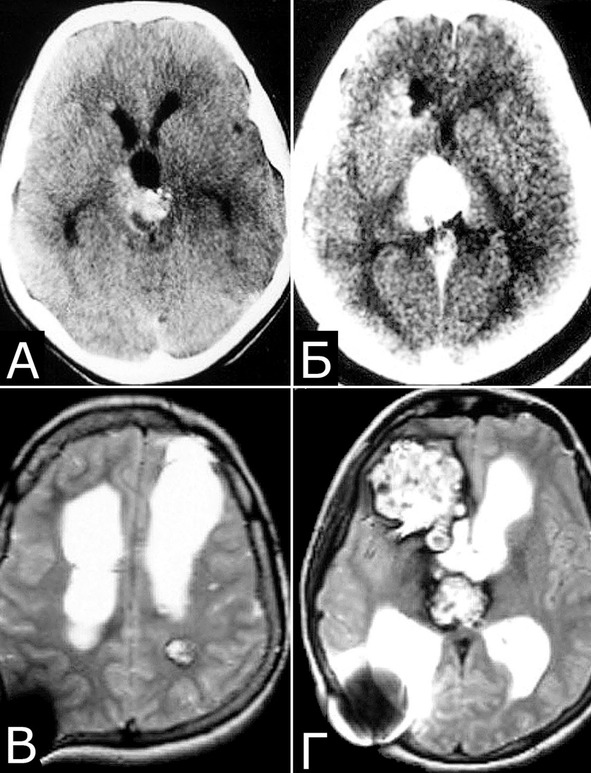

Рис. 30. Б-ная Ш., 1978 г. р. Рост кавернозных мальформаций

Клинический диагноз (б-ная Ш., 1978 г. р.): множественные КМ головного мозга: правой лобной доли; левой лобной доли; левой теменной доли; задних отделов III желудочка. Состояние после удаления КМ левой лобной доли (III гистологический тип). Состояние после установки ВПШ в задний рог правого бокового желудочка. Развитие заболевания и лечение: в возрасте 4 лет ударилась о спинку кровати, появилась тошнота, рвота, тремор и легкая слабость в левых конечностях. При ЛП выявлена кровь в ликворе. Лечилась по м/ж с диагнозом ЧМТ. Восстановилась полностью. С 1984г (6 лет) – периодическая рвота, тремор в руках, нарушение памяти. С 1985г наблюдалась в институте, где по результатам КТ, МРТ и АГ поставлен диагноз: «объемные образования задних отделов III желудочка и левой лобной доли неясного генеза» (А). В 1989 г в связи с очередным ухудшением и нарастанием гидроцефалии выполнена операция: «Удаление объемного образования левой лобной доли. Установка ВПШ в задний рог правого БЖ». Гистологический диагноз: КМ, пролиферативный тип. В 1992 г госпитализирована повторно в связи с усилением головной боли и эпизодом утраты сознания. При КТ выявлено объемное образование в правой лобной доле, незначительное увеличение образования в задних отделах III желудочка (Б). В связи с компенсированным состоянием операция не производилась. В 1999 г приглашена для контрольного обследования. Жалуется на головные боли, иногда со рвотой, дрожание рук, шаткость. Перенесла несколько генерализованных безсудорожных припадков. Благодушна, некритична. Грубо нарушена память на прошедшие и текущие события. Тремор и вычурная поза левой руки, легкая слабость в правой руке. Нарушения походки по типу астазии – абазии. Нет признаков ВЧГ. При МРТ обнаружено значительное увеличение размера КМ правой лобной доли, появление КМ в задних отделах левой теменной доли, стабильные размеры КМ задних отделов III желудочка, нарастание окклюзионной гидроцефалии. Все образования имеют вид, типичный для КМ (В, Г). Была предложена повторная операция, от которой мать больной воздержалась.